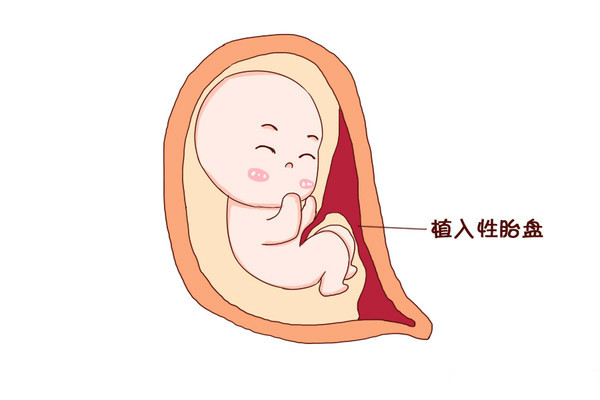

当女性怀孕时,胎盘会在子宫内发育,虽然胎盘的主要功能是为未出生的婴儿提供营养,但有几种胎盘问题会导致流产。胎盘是人体唯一的临时器官,它随妊娠而发展,在妊娠结束后脱...